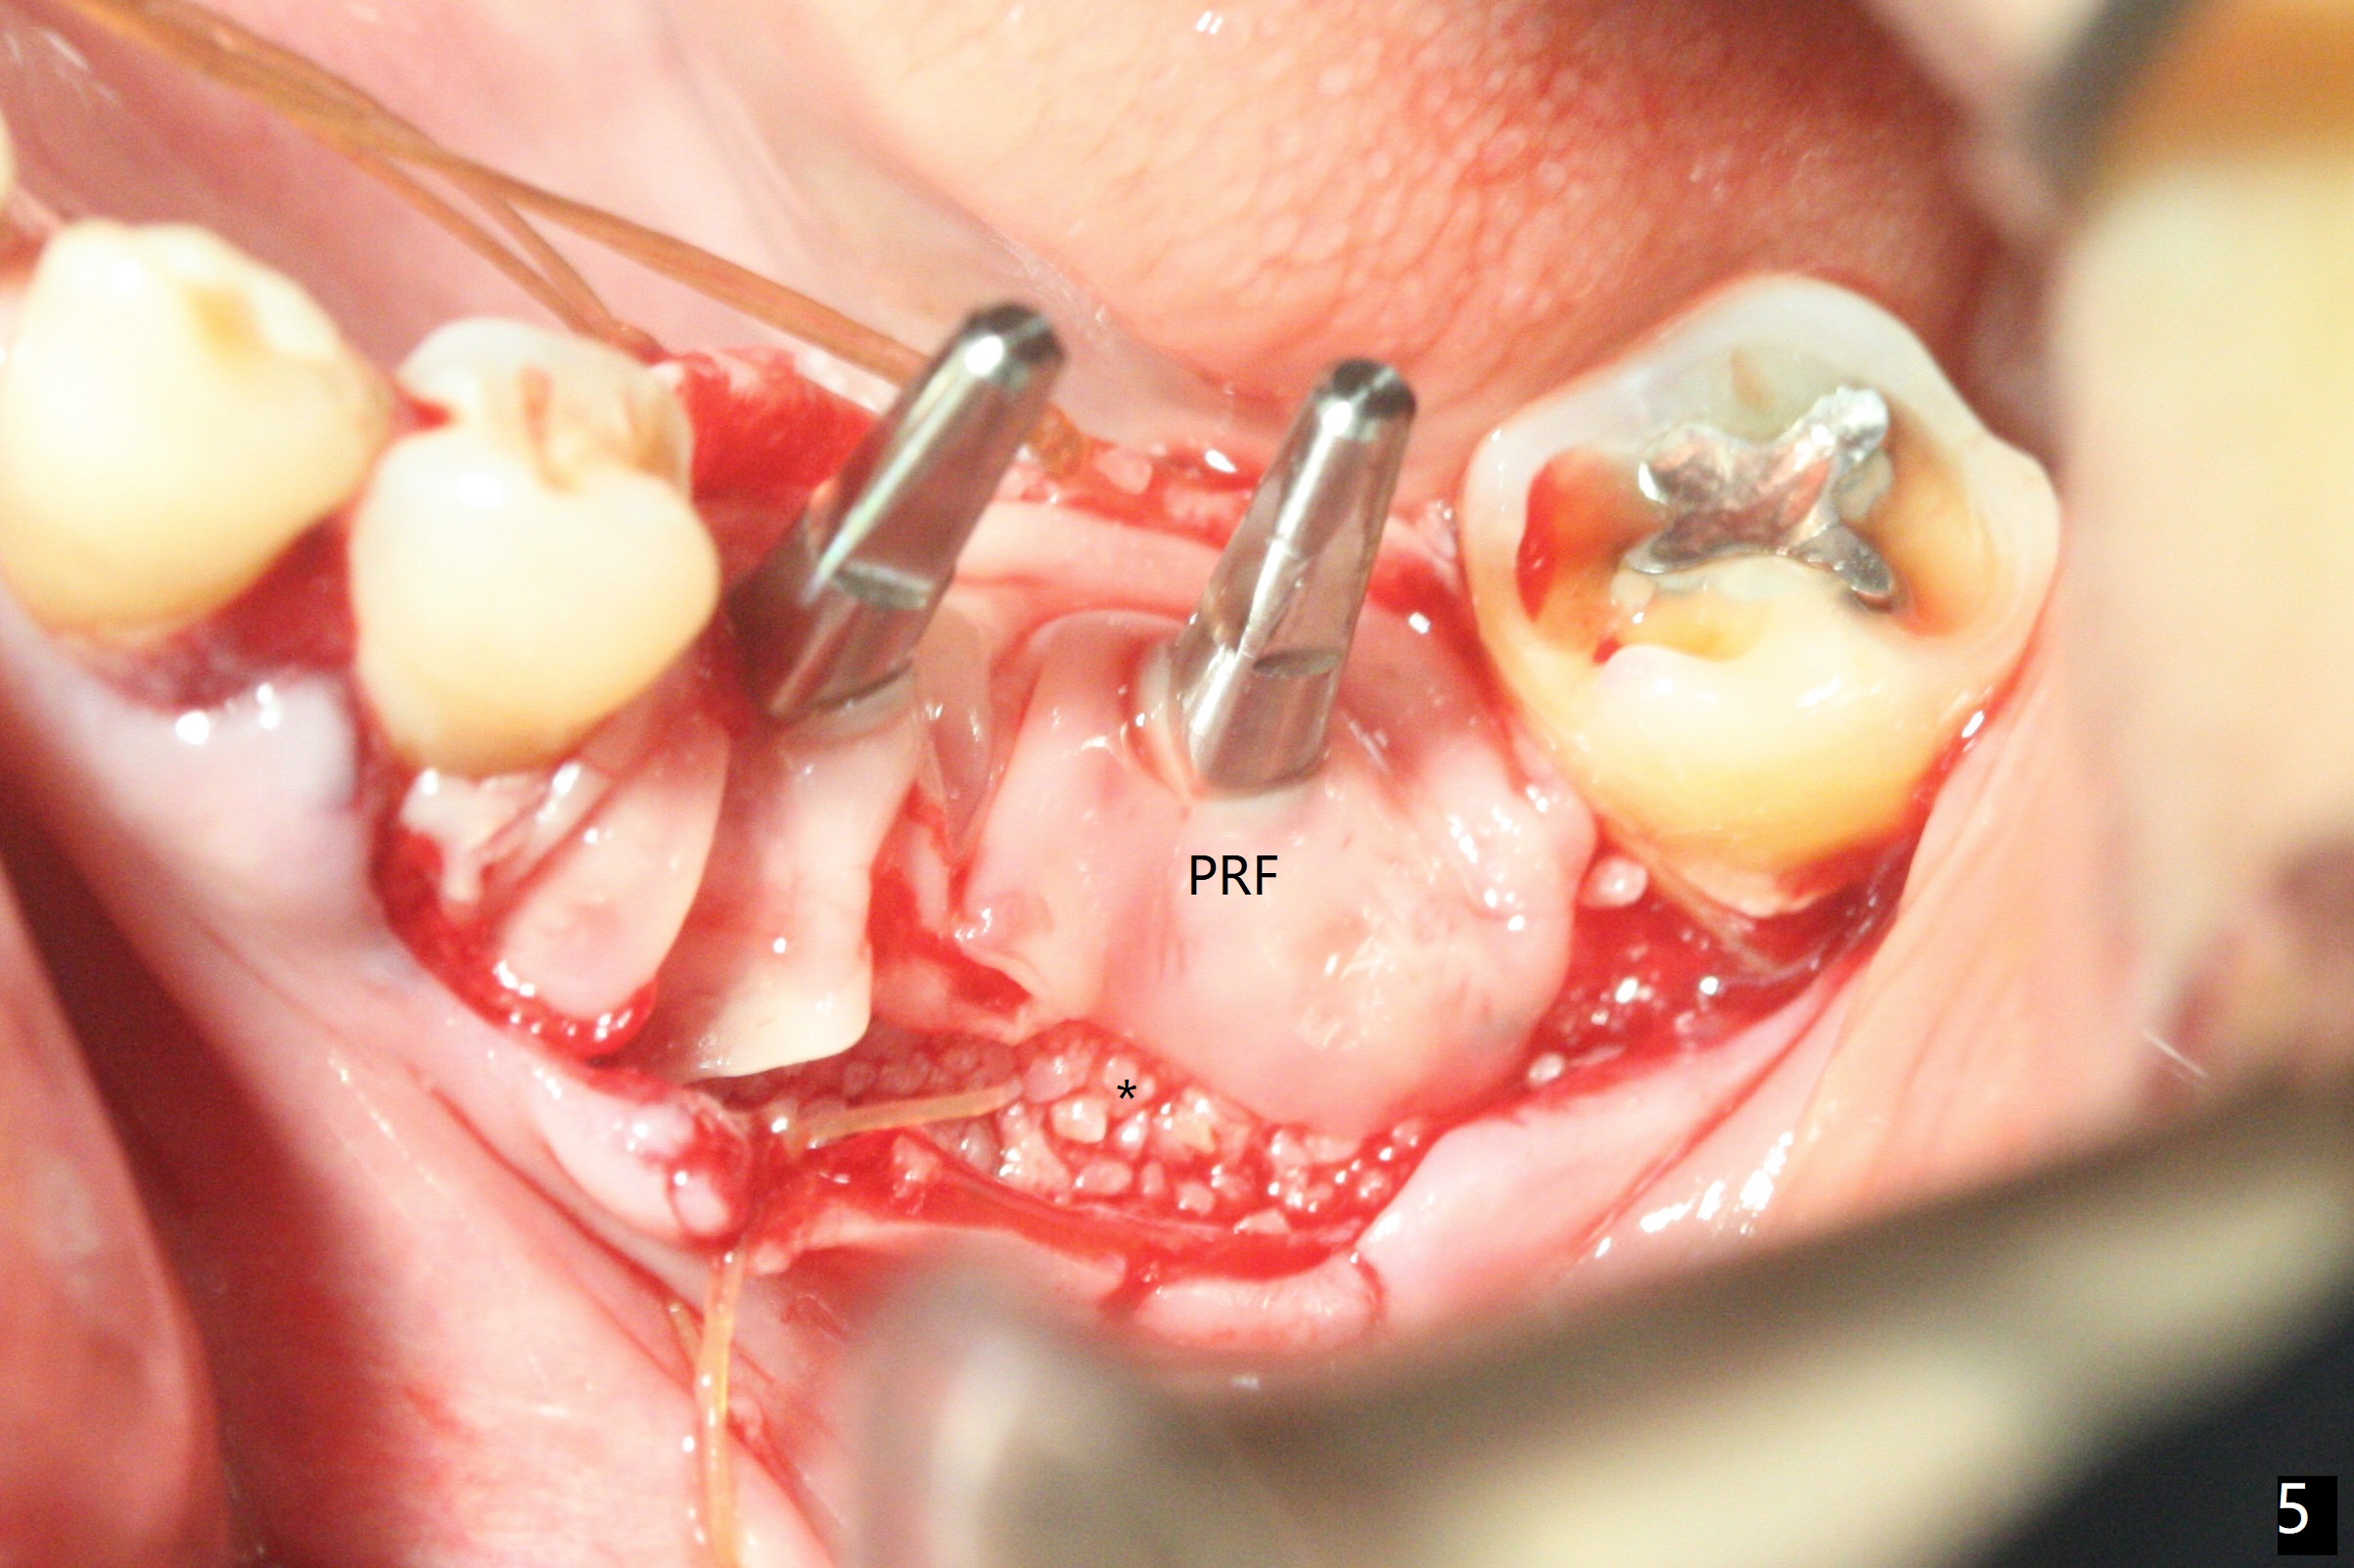

左下5,6切开,使用导板钻洞,都偏向颊侧(图一),好像牙槽嵴太狭窄,不适合做劈开术,然后改为自由手,使用Lindermann(侧方)钻头将钻洞往舌侧迁移,完成一段式植体初步钻洞(图二)以及植体植入(图三:2.5毫米(直径),根据近远中距离,植体不显得太窄)。尽管下齿槽神经阻断麻醉(开始浸润麻醉),病人疼痛明显,不敢下沉远中植体太多(图四:>),放置粘性骨块(图五,六:*)和PRF膜。缝合后,调整基台以及对合牙高度(图六: <),最后放置牙周敷料。由于植骨,术后15天植体周围形成致密的牙龈带(图七:*(gingival band))。术后一个月安置临时连体牙冠,没有任何咬合接触,主要目的防止7近中倾斜。术后三个半月临时牙冠被吞入,右侧托牙也不见了,局部牙龈健康,塞入2-0 gingival retraction cord(增加5基台长度(今后牙冠固位),图八 (>:植体螺丝刀终止地方)),取模。永久性牙冠边缘不重要,由实验室决定。清除残余粘固剂也不是很困难(图九)。